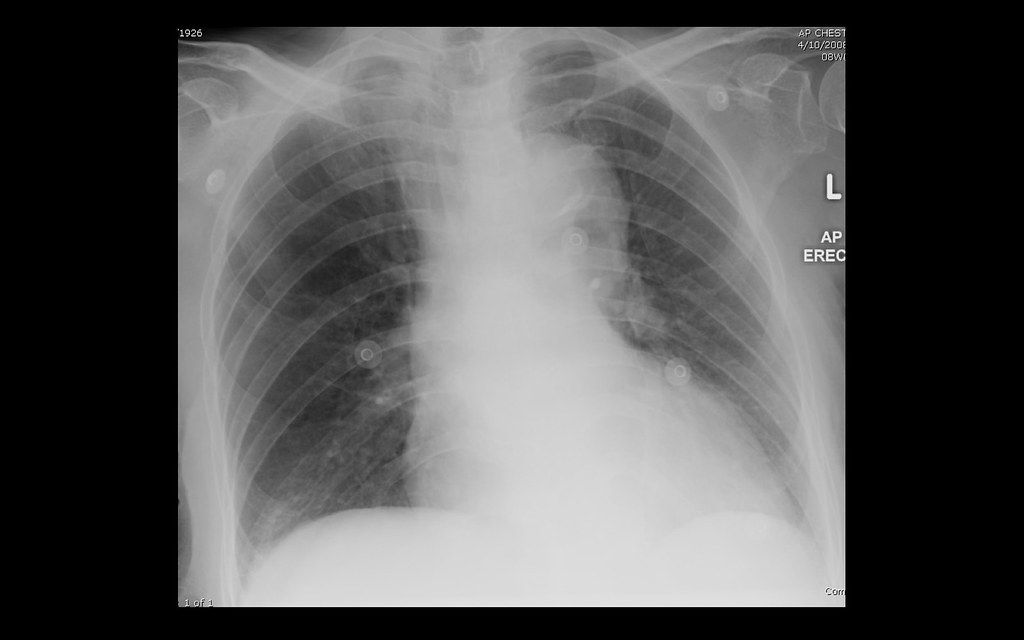

http://3.bp.blogspot.com/-uPzc0naMPZ4/Tw9aYtzFisI/AAAAAAAAAPc/BawBFVRh6fc/s1600/aortic+dissection+X-ray.jpg

Aortic Dissection Without Mediastinal Haemorrhage CXR 1 Flickr

https://c2.staticflickr.com/4/3453/3742801148_e431336c9e_b.jpg

How To Diagnose Aortic Dissection Without Breaking The Bank ACEP Now